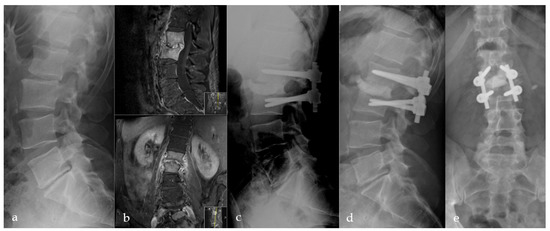

2.2. Surgical Procedure